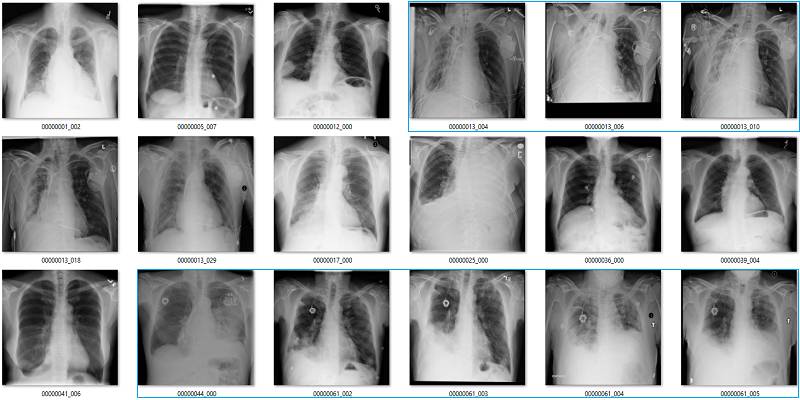

这部分要说该数据集中基于标签的图像。它们是随机选取包含 18 张图像的序列集,并非精挑细选。

我尽量保持谨慎,当一个案例模棱两可的时候,我选择标出标签类别。在所有图像中,红色 = 明显错误的标签;橙色 = 怀疑态度,我没有指出这个问题,但是不能排除这种怀疑。(出于临床诊断的习惯 :p)

气胸(Pneumothorax)

气胸是指在肺部周围的胸膜腔空间有气体。这可能导致肺部瘫痪,因此它是非常严重的病变。但实际上,气胸在 X 光影像上非常微小,经常会被人忽略掉。

初次看来,标签似乎非常有效。在这 18 个样本中,只有用橙色标出的那张影像有点问题,这也可能是因为我没在诊断环境下查看肺部影像的原因。

但是绿框也有点问题,因为这些病人已经使用胸腔引流治疗过气胸。因此,现在有以下两个问题:

这并不是医学上重要的问题,我们希望避免气胸未被诊断出的错误,而这些图像标签确实没有犯这种错误。

如果很多影像都通过胸腔引流治疗,AI 系统将会学习识别胸腔引流而不是气胸。模型训练时的大多数图像样本批量完全可能包含有胸腔引流的气胸。

纤维化

我们已经看到,纤维化的标注准确率非常低。在这些影像中,红框是不正确的标签,橙框是我不确定的标签。在胸腔积液和固结中可能也会出现纤维化,但这些是影像无法告诉我们的。